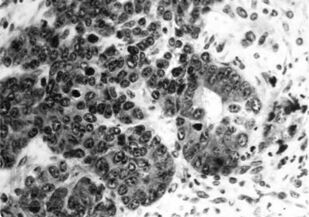

Книга посвящена описанию животных моделей in vivo для отбора, углубленного и/или доклинического изучения цитостатиков, а также некоторых таргетных средств. Представлены основные биологические характеристики, дополненные лекарственной чувствительностью и востребованностью в настоящее время.

Информационный материал предназначен для исследователей, работа которых связана с поиском, углубленным или доклиническим изучением in vivo новых противоопухолевых агентов.